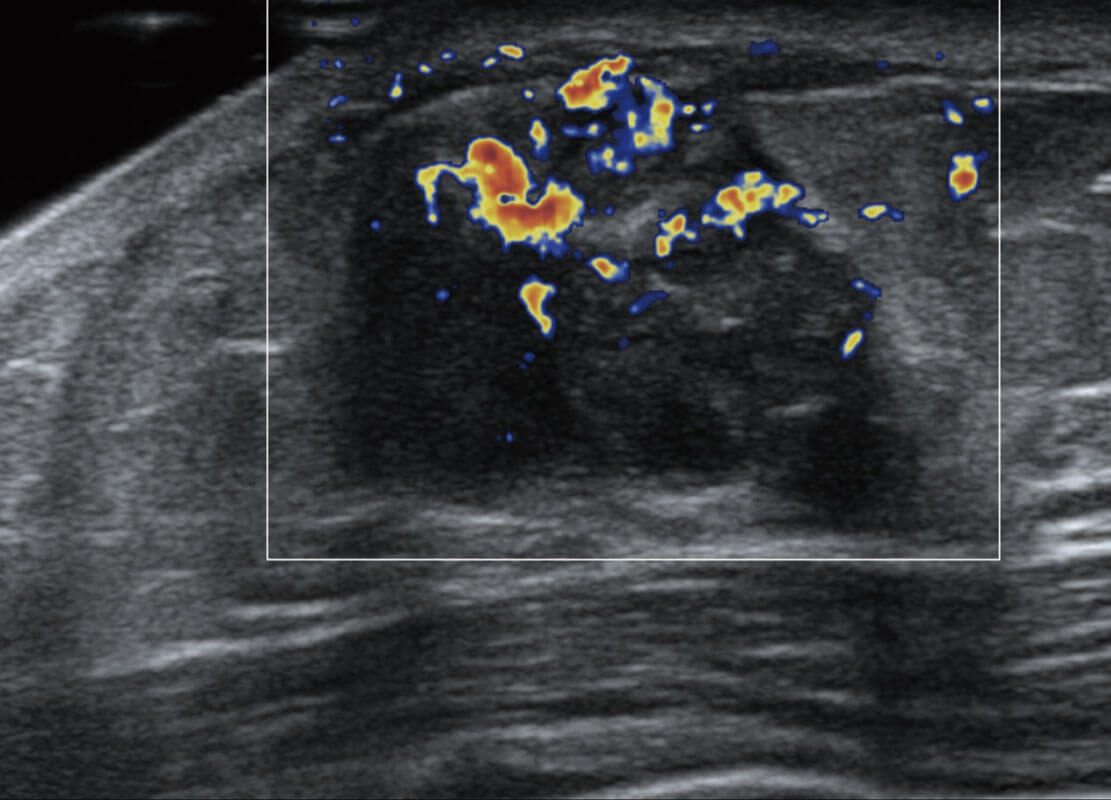

乳腺超声 / 新生儿

P60搭载宽频带线阵探头、宽景成像、弹性成像技术,为您提供乳腺应用方案。P60支持高频相控阵探头、线阵探头、腹部高频探头、腹部微凸探头等,丰富的探头群搭载敏感的彩色血流成像,适用于新生儿多种脏器检测要求,满足新生儿筛查需求。

• 乳腺癌显微血流

• 新生儿肝血管癌